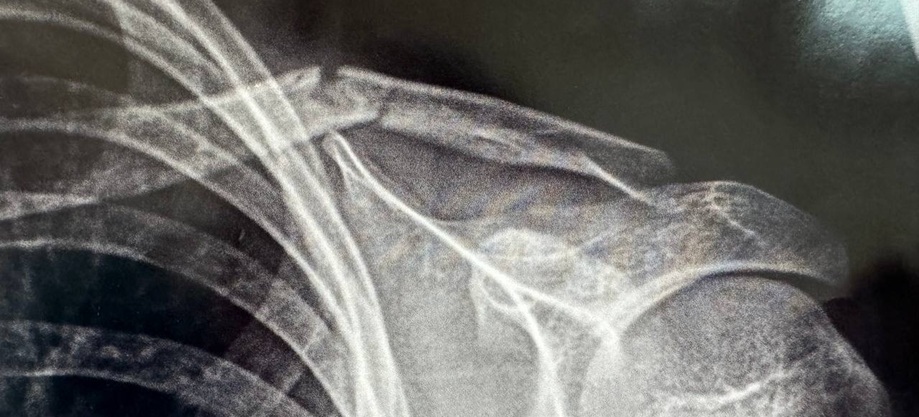

Проведено обстеження, рентгенографія ключиці в 2-х проекціях. Діагноз: закритий перелом ключиці із зміщенням уламків, виконано імобілізацію повʼязкою Дельбе.

На контрольний огляд звернувся до клініки через 10 днів після травми. Виконано рентген контроль. Стан уламків - задовільний.

Через 10 днів проведено контрольне рентген обстеження. Вторинного зміщення уламків не відбулось. Марлево-ватну повʼязку Дельбе замінено на сучасну зручну повʼязку-реклінатор.